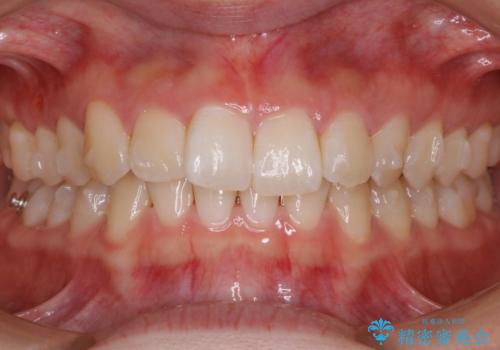

- 初診時、前歯のガタつきを主訴にご来院されました。

精密検査の結果奥歯の噛み合わせのズレからくる前歯のガタつきであることが分かり、患者様と相談した結果、全体をしっかりと治療することをご選択なさったので奥歯から動かして噛み合わせと見た目の両方を治す治療プランとなりました。

下顎の歯は幸いガタつきが少なかったため、下顎を基準とし構成する方針としました。

初診時の写真では一見噛み合わせには問題がないように見えても、実際に精密な検査を行うと改善すべき点が見つかる場合も多くあります。